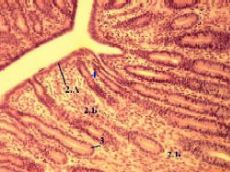

Б. Эндометрий: тканевые компоненты

1. Эндометрий содержит

однослойный призматический эпителий (2.А) и

собственную пластинку (2.Б), которая пронизана маточными железами (3).

2. а) В эпителии матки (как и в эпителии яйцеводов) - два типа клеток:

реснитчатые и

железистые (слизеобразующие).

б) Среднее увеличение

Полный размер

б) При этом реснитчатые клетки

находятся лишь возле устьев маточных желёз и

приобретают реснички (да и то весьма небольшие) только к концу менструального цикла.